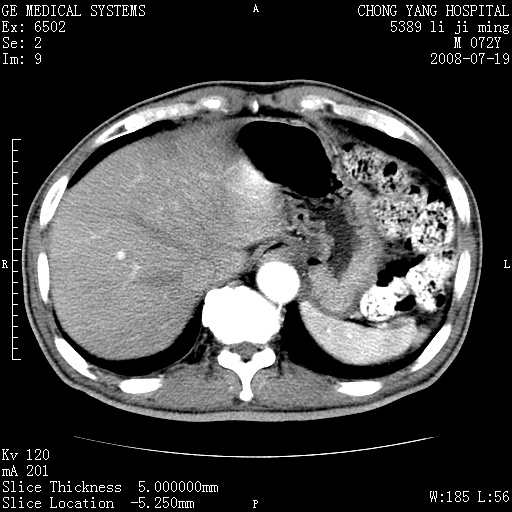

以下是引用zjzjr在2008-7-19 20:57:00的发言:[br]胰头增大,边缘模糊,周围可见渗出影,右侧肾前筋膜增厚.支持胰腺炎.

以下是引用不学无术在2008-7-19 23:15:00的发言:[br]胰腺增大尤以胰头明显,边缘模糊,周围可见渗出影,右侧肾前筋膜增厚,肠管於涨.支持胰腺炎